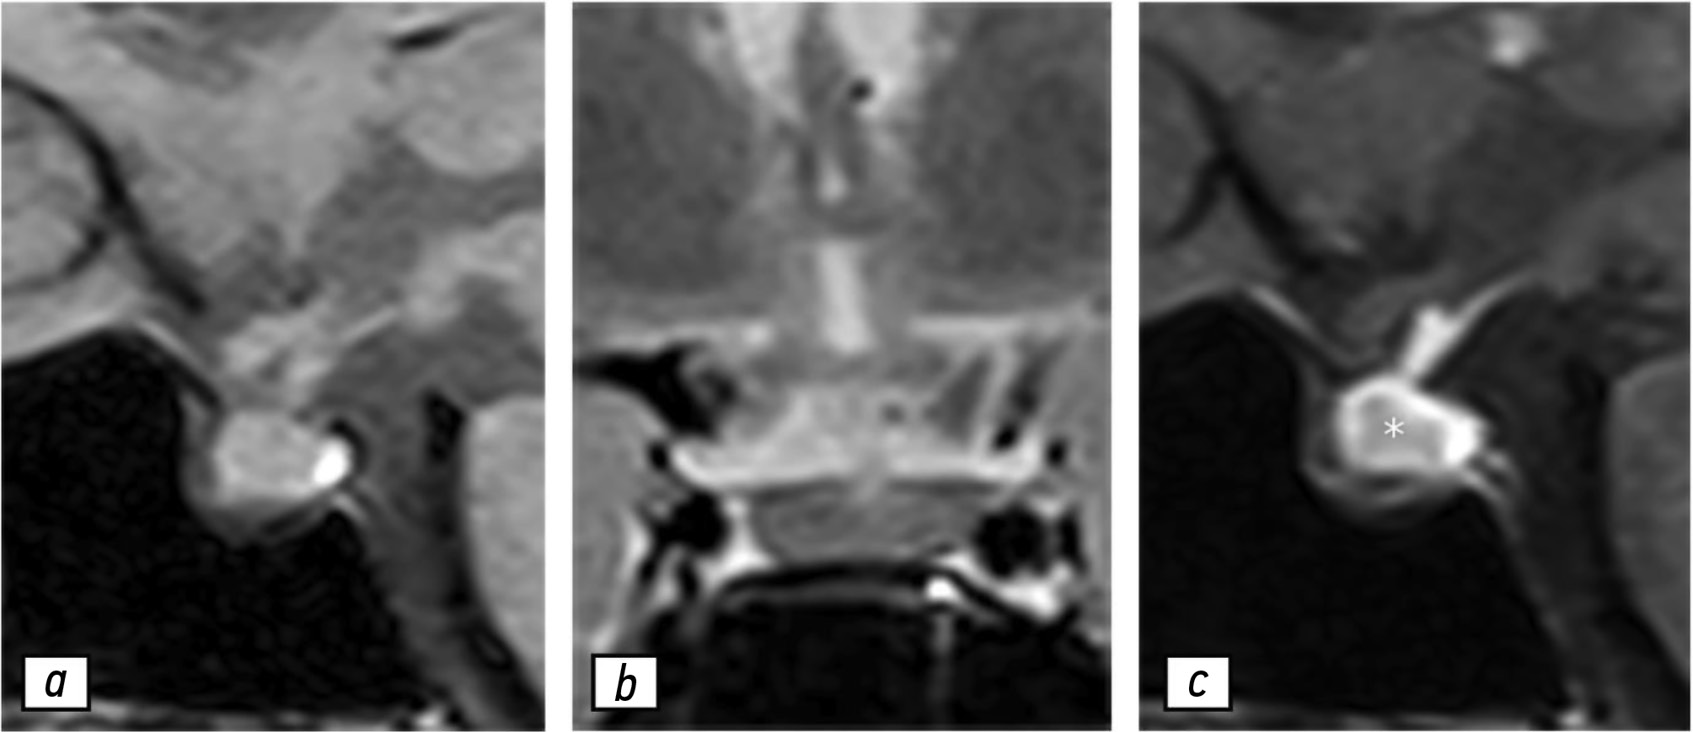

В статье представлено описание клинического случая заболевания у женщины 37 лет с гиперпролактинемией в анамнезе, получавшей симптоматическое лечение каберголином. Её направили на проведение магнитно-резонансной томографии, результаты которой продемонстрировали гетерогенность сигнала в области гипофиза. При выполнении контрольной магнитно-резонансной томографии в июле 2021 г. отмечены гетерогенность и увеличение гипофиза. В декабре 2021 г. у пациентки на фоне COVID-19 диагностировали тяжёлую пневмонию. В качестве лечения ей назначили глюкокортикостероиды и кислородную терапию. В мае 2022 г. результаты магнитно-резонансной томографии продемонстрировали выраженное увеличение гипофиза и гетерогенность его структуры. Значимое улучшение клинических и радиологических проявлений отмечено после назначения преднизона (утром и вечером — 10 и 5 мг соответственно). Пациентка находилась под наблюдением до завершения пандемии COVID-19.